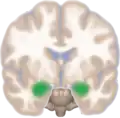

Frontal view of the amygdala in an average human brain